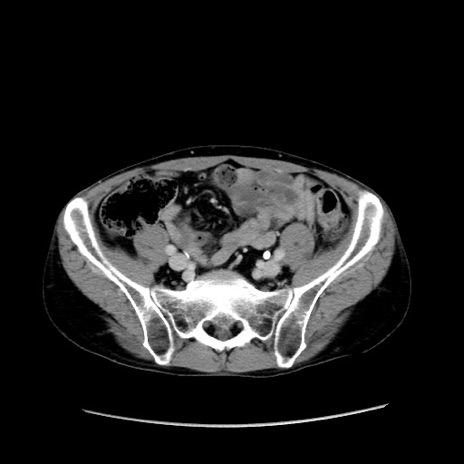

【症例】40歳代 男性

【主訴】腹痛

【現病歴】4時間ほど前に電車に乗車中に臍部上より腹痛出現。徐々に増悪し起立困難となり、救急外来受診。生ものは数日食べていない。今朝お雑煮を食べた。

【身体所見】BT 36.8℃、BP 117/84mmHg、HR 91/min、SpO2 97%、苦悶様、腹部:臍上部広範囲圧痛あり、反跳痛±

【データ】WBC 8100、CRP 0.03